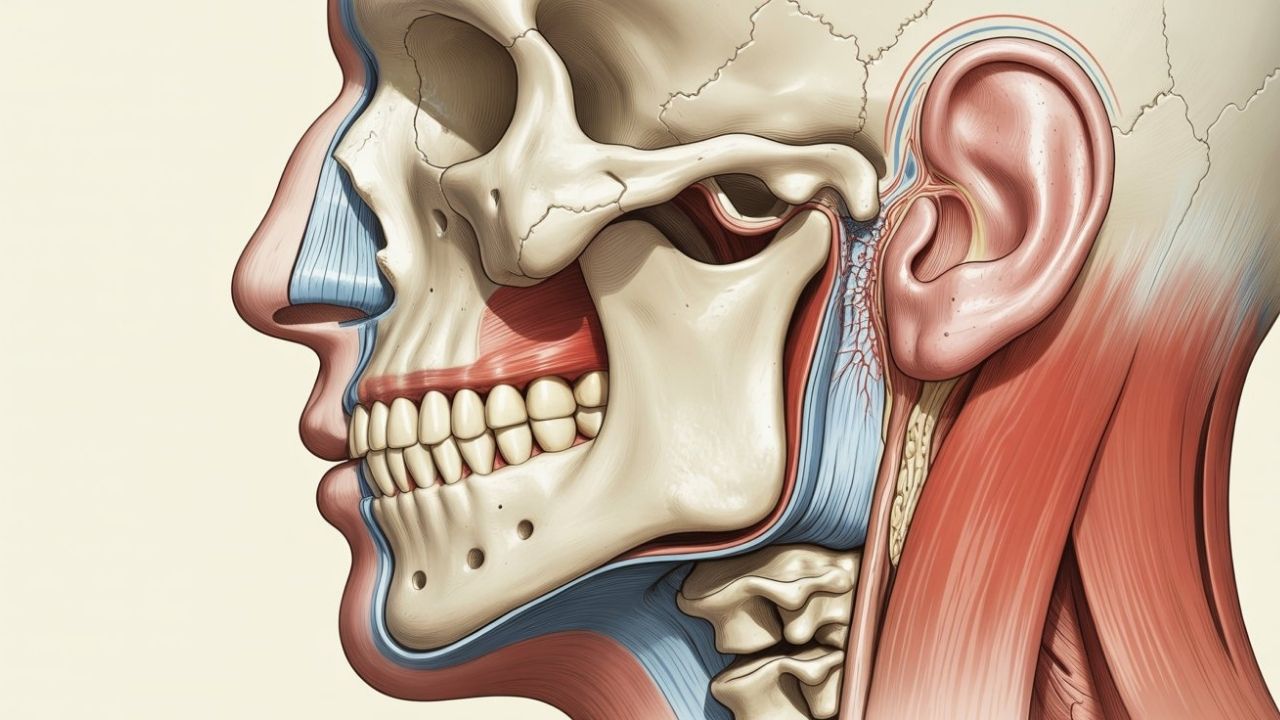

Understanding the Temporomandibular Joint

The temporomandibular joint is one of the most complex joints in the human body. It allows both hinge-like and sliding movements, enabling the jaw to move up and down, side to side, and forward. Because of this complexity, the joint is vulnerable to stress, injury, and muscular imbalance.